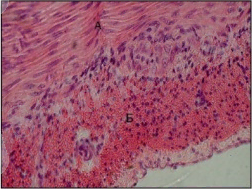

Тканьдік гомеостаз, эпидермистің тұрақтылығын қамтамасыз ететін факторлар

Әрбір тін өзінің құрылымдық бірлігімен, тұрақтылығымен(гомеостаз) және өзінің санымен ерекшеленеді. Тіндік гомеостаздың негізін жасушаның жаңаруы және оның өлімі қамтамасыз етеді.

Эпимидермістің тұрақтылығы мен құрамы осы механизмдер ақылы реттеледі. Алайда, эпидермис тіндердің саралау бірегей мүмкіндігі бар шекара болып табылады, бұл шын мәнінде, оған гомеостаз бетінен корниоциттер бағытталған жасуша көші-қон және дифференциалауы сияқты маңызды құбылыс болып табылады.